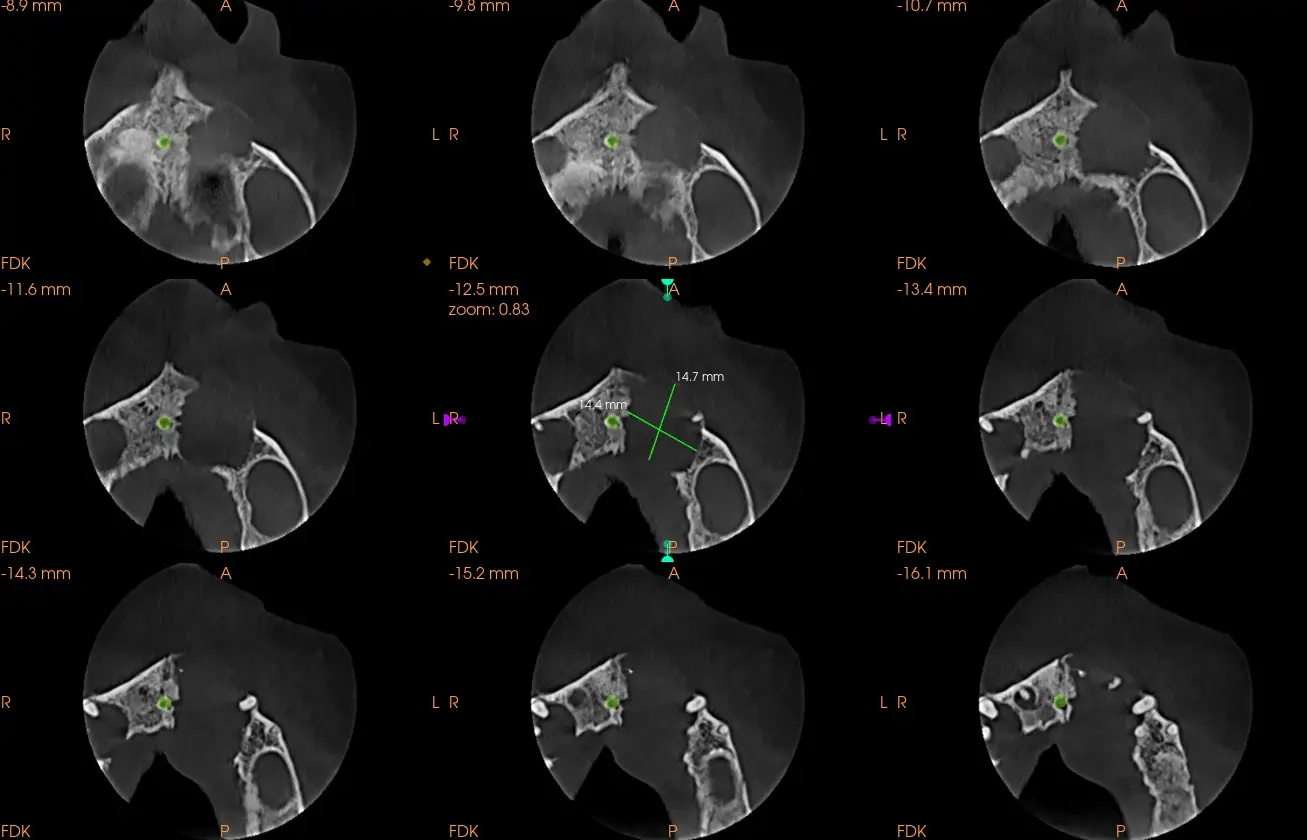

Al realizarle la tomografía se observó una imagen hipodensa (Fig. 1 y 2) proveniente de la pieza dental 21, pieza en la que fue realizada un tratamiento de conducto, donde se llega a observar una sobre obturación (Overfilling) (Fig. 3 y 4), el material hiperdenso se observa sobresalir del ápice radicular sobrepasando el limite CDC (conección Dentino-Cementaria) , generando el quiste periapical. ( Fig. 5). El quiste va generando presion a las piezas adyacentes y se extiende desde pieza dental 21 a 23 inclusive.

Se describe la tipica imagen expansiva sobre los tejidos scircundantes, tipo globo con agua, que tiene limites bien definidos, aunque por su tamaño y posibles reagudizaciones en algunas zonas se encuentra ausente o cueste distinguirlo, provocando ensanchamiento de las tablas libres y adelgazamiento